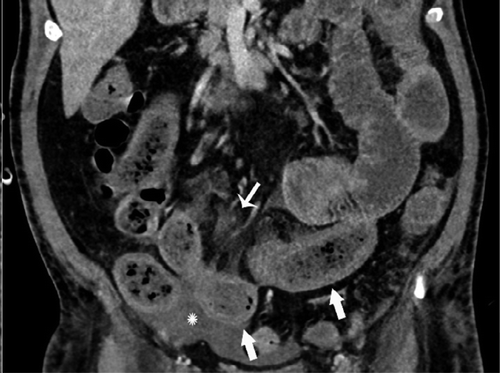

В частности, как пояснил специалист, у некоторых пациентов с COVID-19 внезапно развивался пневматоз - патологическое состояние системы пищеварения, при котором газы проникают в толщу стенки кишечника и образуют там воздушные кисты. Кроме того, у нескольких людей было выявлено необычное желтое обесцвечивание кишечника, еще у трех больных - инфаркт кишечника.

© Radiology